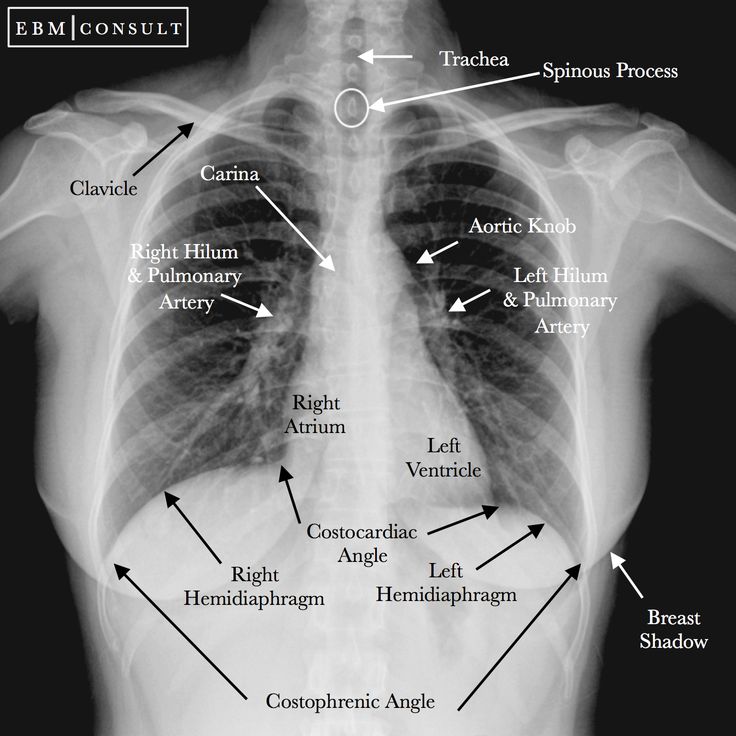

An Electrocardiogram (ECG) indicated ST-segment elevation in leads II, III, and aVF, suggestive of a heart attack. Cardiac Enzyme Studies confirmed myocardial damage with elevated troponin levels, while a Chest X-ray ruled out any lung complications.

Image of Cardiac Arrest Width